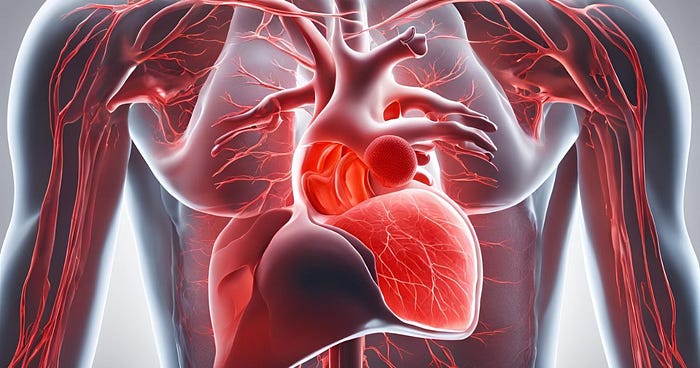

2. Cardiovascular Diseases

Cardiovascular diseases (CVDs) remain the leading cause of death worldwide, and the numbers are rising. Poor lifestyle choices, such as unhealthy diets, sedentary behavior, and smoking, contribute to this trend. Obesity, diabetes, and high cholesterol are additional risk factors. With more people working from home and a general increase in sedentary behavior, CVDs will continue to be a growing concern in the next few years.